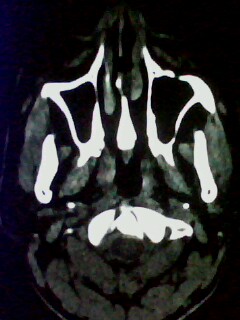

以下是引用随光逐影在2009-5-20 19:22:00的发言:[br]1)考虑左上颌骨近中线区含牙囊肿。2)鼻中隔右突偏曲。3)双侧下鼻甲肥大。